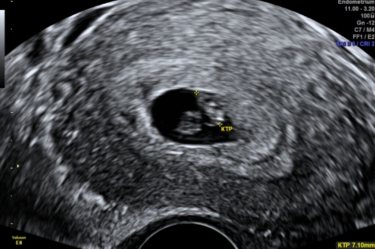

Сегодня первый раз была на узи. У нас бьётся сердечко (я его слышала). Развиваемся хорошо, по срокам.... так переживала, после зб и выкидыша. В среду иду к гинекологу.